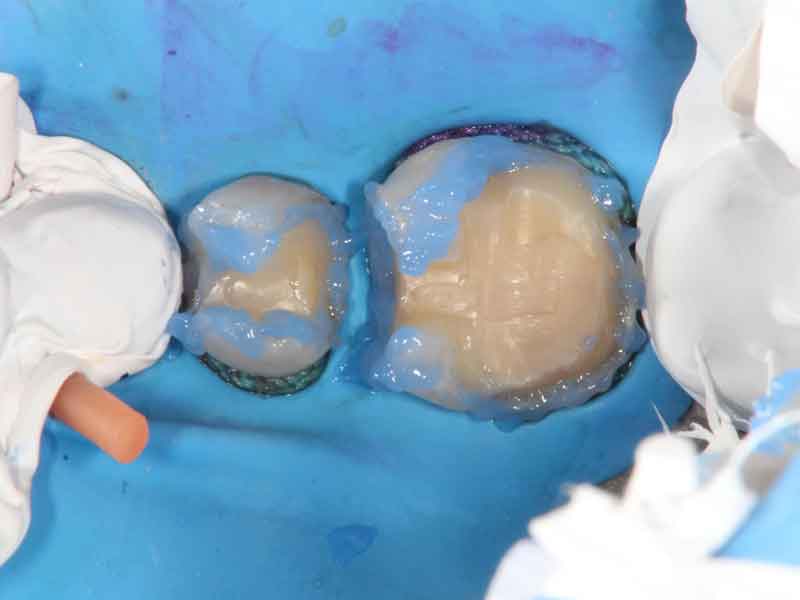

う蝕検知液(虫歯を染め出す薬液)を使い、虫歯の部分を歯科用顕微鏡下で、丁寧に削ります。

2.健康な歯の神経を温存

外側の虫歯を除去したら、まずは隔壁と呼ばれる壁を樹脂で作ります。 隔壁にラバーダム防湿のバネをかけることで、唾液の入り込まない無菌環境を作ることができます。 無菌環境を作ってから、神経に近い部分の虫歯を慎重に削っていきます。 削っていくと歯の神経が露出してきました。マイクロスコープ(歯科用顕微鏡)を使用して痛んでいる歯の神経を除去し、健康な歯の神経を温存します。

3.MTAセメントで覆う

神経が露出している部分をMTAセメントで覆います。

4.樹脂で埋める

最後に窩洞を樹脂で埋めます。 経過観察後、歯を削った量に応じてコンポジットレジン修復、あるいはセラミックによる接着修復を行って終了です。 この方は神経を抜かずに残すことができました。

マイクロスコープを使用した診療イメージ

20倍の拡大視野で観察すると、虫歯や歯石などを細かく観察できます。

痛んでいない歯の神経はこのように点状に毛細血管が見え、出血は5分以内に止まります。歯の神経が痛んでいるか痛んでいないかを見極めるためには、マイクロスコープ(歯科用顕微鏡)の使用が必須です。